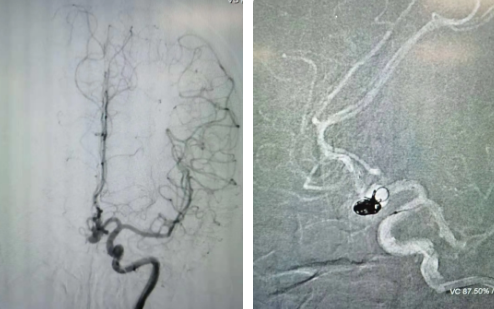

經(jīng)過全面仔細(xì)評(píng)估,西安國際醫(yī)學(xué)中心醫(yī)院神經(jīng)外科陸丹醫(yī)生決定采用微創(chuàng)介入進(jìn)行治療。在取得患者及家屬同意后,3月11日,陸丹醫(yī)生為患者行Atlas支架輔助顱內(nèi)動(dòng)脈瘤栓塞術(shù)。

腦血管較外周血管更為脆弱、迂曲,對術(shù)者的操作技術(shù)及精準(zhǔn)性要求特別高。術(shù)中,陸丹醫(yī)生通過股動(dòng)脈穿刺、置入微導(dǎo)管,再通過微導(dǎo)管將彈簧圏送入動(dòng)脈瘤腔內(nèi),利用彈簧圈的機(jī)械閉塞作用,達(dá)到防止動(dòng)脈瘤破裂的目的。術(shù)后,患者各項(xiàng)生命體征平穩(wěn)。

陸丹醫(yī)生介紹,此次腦科醫(yī)院首次采用Atlas支架輔助進(jìn)行顱內(nèi)動(dòng)脈瘤栓塞術(shù)。以往動(dòng)脈瘤栓塞術(shù)中的支架輸送導(dǎo)管較粗,支架順應(yīng)性差,易使載瘤動(dòng)脈移位,而Atlas支架的輸送導(dǎo)管很細(xì),輸送順滑,同時(shí)順應(yīng)性及貼壁性強(qiáng),能夠適應(yīng)迂曲的腦遠(yuǎn)端血管。